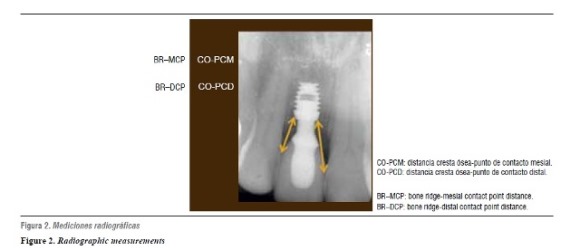

Además, se tomó una radiografía periapical a cada uno de los implantes involucrados, inmediatamente después de instalada la restauración definitiva y a los 6 meses, necesaria para evaluar la anatomía y altura de los tejidos óseos adyacentes al implante y establecer los cambios durante el periodo de observación. La radiografía al momento de la instalación de la restauración se consideró como el punto de partida y permitió evaluar los cambios radiográficos posteriores a la carga del implante. La evaluación radiográfica se hizo con la técnica paralela, utilizando un posicionador Rinn® (XCP® Instruments, Elgin, IL) junto con un equipo de rayos X (Trophy CCX Digital®) (f = 3, 70 kV, 8 mA) y se hizo el proceso en un revelador automático (Air Techniques®-Melville, NY). Se utilizó el sofware Axiovision® (Wright, Toronto Canadá) para la evaluación digital de las radiografías donde se estableció la distancia desde la cresta ósea hasta el punto de contacto mesial (CO-PCM) y distal (CO-PCD) (figura 2). Todas las radiografías fueron estandarizadas en cuanto angulación, para lo cual se confeccionó una férula para cada paciente.